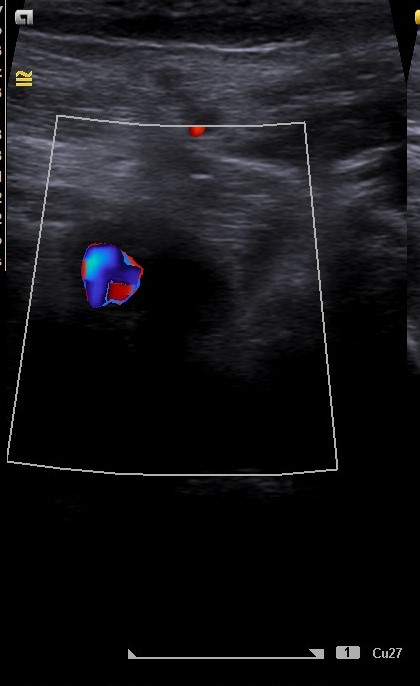

Hallazgos ecográficos

El estudio pone de manifiesto una ocupación trombótica aguda de la vena poplítea de pierna izquierda.

En el estudio se comparó la vena poplítea derecha, la cual a la presión ejercida con la sonda del ecógrafo sí comprimía, lo cual no sucedía con la vena poplítea izquierda.

Ambas venas femorales bilaterales eran permeables.

No fueron necesarias otras pruebas dado que la ecografía fue diagnóstica.